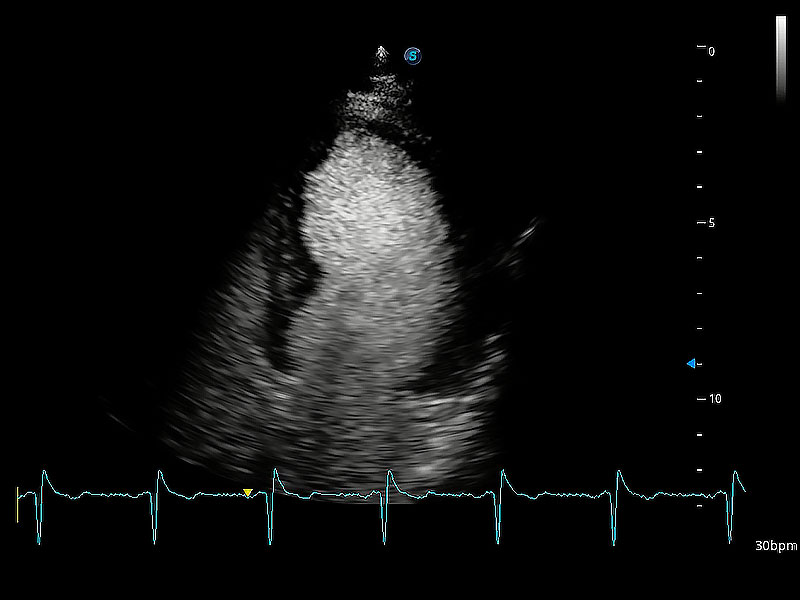

ProPet 80 配备了丰富的心脏探头群、先进的成像技术和专业的心脏测量工具,可帮助动物医生为不同体型和生理结构的动物提供心脏和心肌功能的全面评估。

ProPet 80 专为动物医生设计,对不同的动物体型和生理结构作出了针对性的优化。通过动物影像专用软件,可满足个性化的应用需求,帮助动物医生获得更精确的诊断数据。